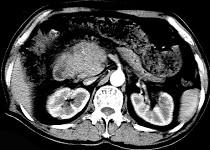

问题 男50岁黄疸进行性加重、腹部胀痛不适、食欲减退、体重减轻、上腹部可触及肿块,CT如图,最可能的诊断为 ( )

选项 A.急性胰腺炎 B.慢性胰腺炎 C.胰头癌 D.腹膜后淋巴瘤 E.转移瘤

答案 C